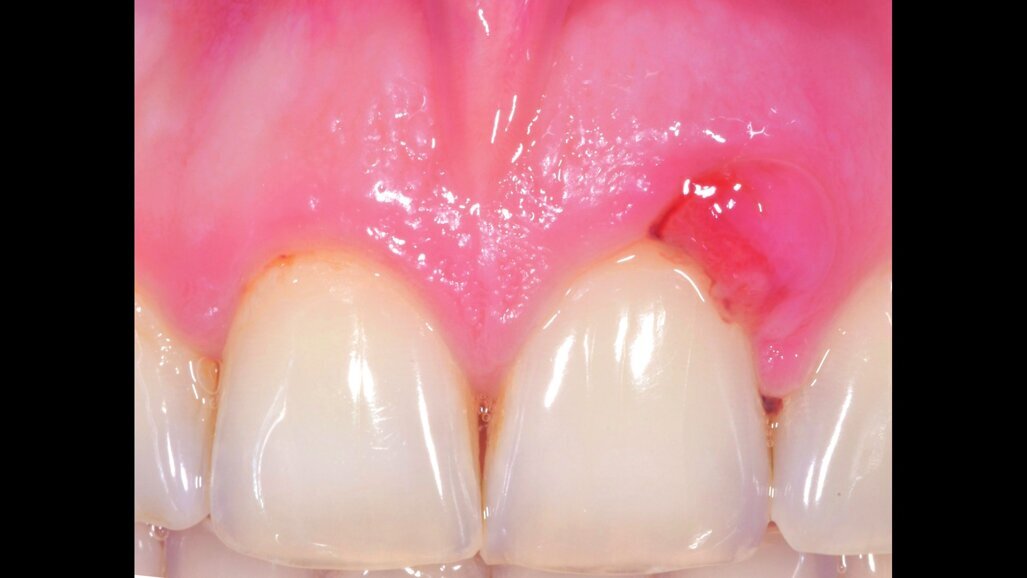

Il paziente di anni 33 viene inviato per trattamento di un gonfiore gengivale apparso circa 1 mese prima. È stato trattato con scaling e root planing senza ottenere il risultato voluto. All’esame obiettivo presenta una lieve gengivite interprossimale con infiammazione e gonfiore limitato alla parte vestibolare di 2.1 con sondaggio di 5 mm vestibolare e 7 mm disto-vestibolare (Fig. 1). La superficie della radice era stata strumentata una settimana prima e si presenta senza residui di tartaro e senza riassorbimenti esterni. Viene scelta l’applicazione di Ozosan Gel per ridurre subito i sintomi che limitavano la capacità del paziente di applicare una corretta igiene orale e per la sua azione antibatterica ma anche stimolante la guarigione. Ozosan Gel viene applicato per 8 minuti - azione anti batterica - seguito da lavaggio con fisiologica. Da subito il paziente segnala riduzione del dolore e viene istruito a uno spazzolamento delicato a roll con spazzolino morbido. Viene rivisto dopo 2 giorni ed effettuata una nuova applicazione di ozono. Controllo a 5 gg (Fig. 2), e applicazione di Ozosan Gel per due minuti per stimolare la guarigione (Fig. 3). Controllo a 2 sett. (Fig. 4) dove si nota recessione dei tessuti che erano stati strumentati in modo aggressivo. Guarigione a due mesi dove i tessuti stanno ricoprendo la recessione (Fig. 5).

Fig. 1 - Aspetto clinico del paziente alla prima visita. Viene applicato Ozosan® per 8 min e lavato con fisiologica.